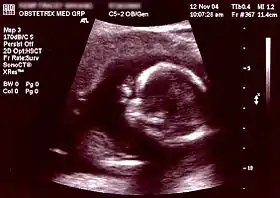

| Ultrasound[8] | Periodically | Non-invasive/Invasive | Abdominal or Transvaginal | ~1 day - ~1 week | Fetal development, neural tube defects, birth defects, and various other physical abnormalities (see below for specific ultrasound tests) | NA | |

First/Second/Third trimester Screen

The first, second, combined, and third trimester screens typically consist of an ultrasound (abdominal and/or transvaginal) and maternal blood/serum testing. The ultrasound is used to visually assess the growth, development, and activity of the fetus through imaging observations and measurements. The ultrasound portion of the first trimester screen can include a nuchal translucency screen and a fetal nasal bone determination screen. The available blood tests from the first trimester screen can test for plasma protein A and human chorionic gonadotropin. The second trimester screen looks at specific blood markers, to include the estriol, inhibin and human chorionic gonadotropin hormones and often consists of Alpha-fetoprotein (AFP) screening. Any abnormal results from these screening tests can indicate the possibility of abnormal conditions such as Trisomy 18, Trisomy 21 (Down syndrome), and spina bifida.[13]

| Non-invasive | Ultrasound detection | Commonly dating scans (sometimes known as booking scans or dating ultrasounds) from 7 weeks to confirm pregnancy dates and look for multiple pregnancies. The specialised nuchal scan at 11–13 weeks may be used to identify higher risks of Downs syndrome. Later morphology scans, also called anatomy ultrasound, from 18 weeks may check for any abnormal development. Additional ultrasounds may be performed if there are any other problems with the pregnancy, or if the pregnancy is post-due. | First or second trimester |

The anomaly scan is performed between 18 and 22 weeks of gestational age. The International Society of Ultrasound in Obstetrics and Gynecology (ISUOG) recommends that this ultrasound is performed as a matter of routine prenatal care, to measure the fetus so that growth abnormalities can be recognized quickly later in pregnancy, and to assess for congenital malformations and multiple pregnancies (i.e. twins).[75] The scan can detect anencephaly, open spina bifida, cleft lip, diaphragmatic hernia, gastroschisis, omphalocele, congenital heart defect, bilateral renal agenesis, osteochondrodysplasia, Edwards syndrome, and Patau syndrome.[76]